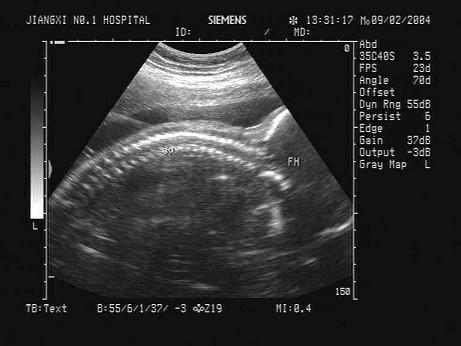

问题 根据胎儿声像图,可见清晰脊柱和头颅光环,该胎儿至少应大于多少周?(?)

选项 A.12周 B.8周 C.6周 D.28周 E.32周

答案 A